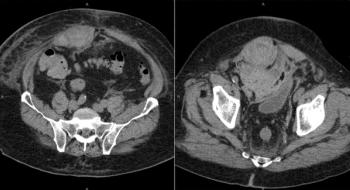

A 30-year-old man who recently underwent induction chemotherapy for bone marrow transplant is admitted with neutropenia and right lower-quadrant abdominal pain. What is your diagnosis?